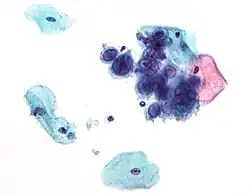

Злокачественные опухоли

Вирусы могут вызывать злокачественные новообразования (в частности, гепатоцеллюлярную карциному или саркому Капоши) у человека и других видов, хотя они возникают лишь у небольшой части инфицированных. Опухолеродные вирусы относятся к различным семействам; они включают и РНК-, и ДНК-содержащие вирусы, поэтому единого типа «онковирус» не существует (устаревший термин, первоначально применявшийся для быстро трансформирующихся ретровирусов). Развитие рака определяется множеством факторов, такими как иммунитет хозяина[181] и его мутации[182]. К вирусам, способным вызывать рак у человека, относят некоторых представителей папилломавируса человека, вируса гепатита B и C, вируса Эпштейна — Барр, герпесвируса саркомы Капоши и человеческого T-лимфотропного вируса. Совсем недавно открытым вирусом рака человека является полиомавирус (полиомавирус клеток Меркеля), который в большинстве случаев вызывает редкую форму рака кожи, называемого карциномой клеток Меркеля[183]. Вирусы гепатита могут вызвать хроническую вирусную инфекцию, которая приводит к раку печени[184][185]. Заражение человеческим T-лимфотрофным вирусом может привести к тропическому спастическому параперезу и зрелой лейкемии Т-клеток[186]. Человеческие папилломавирусы могут вызывать рак шейки матки, кожи, ануса и полового члена[187]. Из герпесвирусов герпесвирус саркомы Капоши вызывает саркому Капоши и лимфому полости тела, вирус Эпштейна — Барр — лимфому Беркитта, лимфогранулематоз, нарушения B-лимфопролиферации и назофарингеальную карциному[188]. Полиомавирус клеток Меркеля близок к вирусу SV40 и полиомавирусам мышей, которые более 50 лет использовались как животные модели для изучения вирусного рака[189].